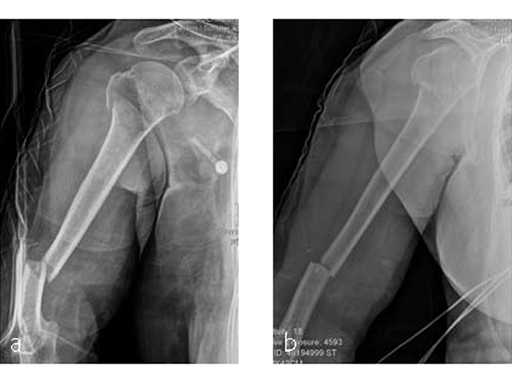

Case 5: Staircase fall

Following a fall downstairs, a 70-year-old woman sustained a head injury with intracerebral and subdural haematoma, as well as a complex fracture of the right humerus, representing a minimal displaced proximal and an oblique fracture in the distal part of the humerus (Fig 11).

After neurosurgical intervention, surgery of the humerus was planned 10 days after the index trauma. The patient was still at the neurological intensive care unit and a preoperative clinical examination of the patient, regarding radial nerve palsy, was not possible. Therefore, a surgical revision with exploration of the radial nerve and an osteosythesis of the humerus using a long MultiLoc Humeral Nail was indicated.

The patient was operated on in beach chair position. For the exploration of the radial nerve, a limited anterolateral approach was used. The nerve was mobilized and retracted laterally. An anterolateral approach to the proximal humerus was performed. The supraspinatus showed a small acute rupture without retraction. The supraspinatus tendon was split to get access to the insertion area on the humeral head. A 270 mm long MultiLoc Humeral Nail of 8.5 mm diameter was inserted under visual and x-ray control to the desired endpoint. Reduction of both the proximal and the distal humerus fracture was anatomical. In the lateral view there was a small gap, and it was decided to apply compression after distal locking (Fig 12). Proximally, three MultiLoc screws were inserted and a 2 mm end cap was placed. Finally, the supraspinatus rupture was reconstructed with transosseous sutures and secured with an augmentation plate. The posterior greater tuberosity fracture was secured with Fiber Wire to the MultiLoc screws. Fig 13 illustrates the definitive fixation.

Postoperatively, no sling was used because the patient stayed in medically induced coma.